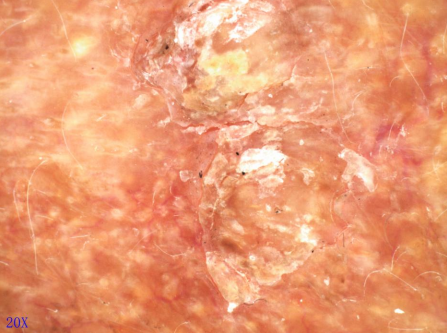

皮肤镜下表现为明显的“草莓征”,表面角化鳞屑明显。张医生告知阿姨家人,“日光性角化病”的可能性大,建议皮肤病理检查。家人表示知晓,完善了后续的检查。